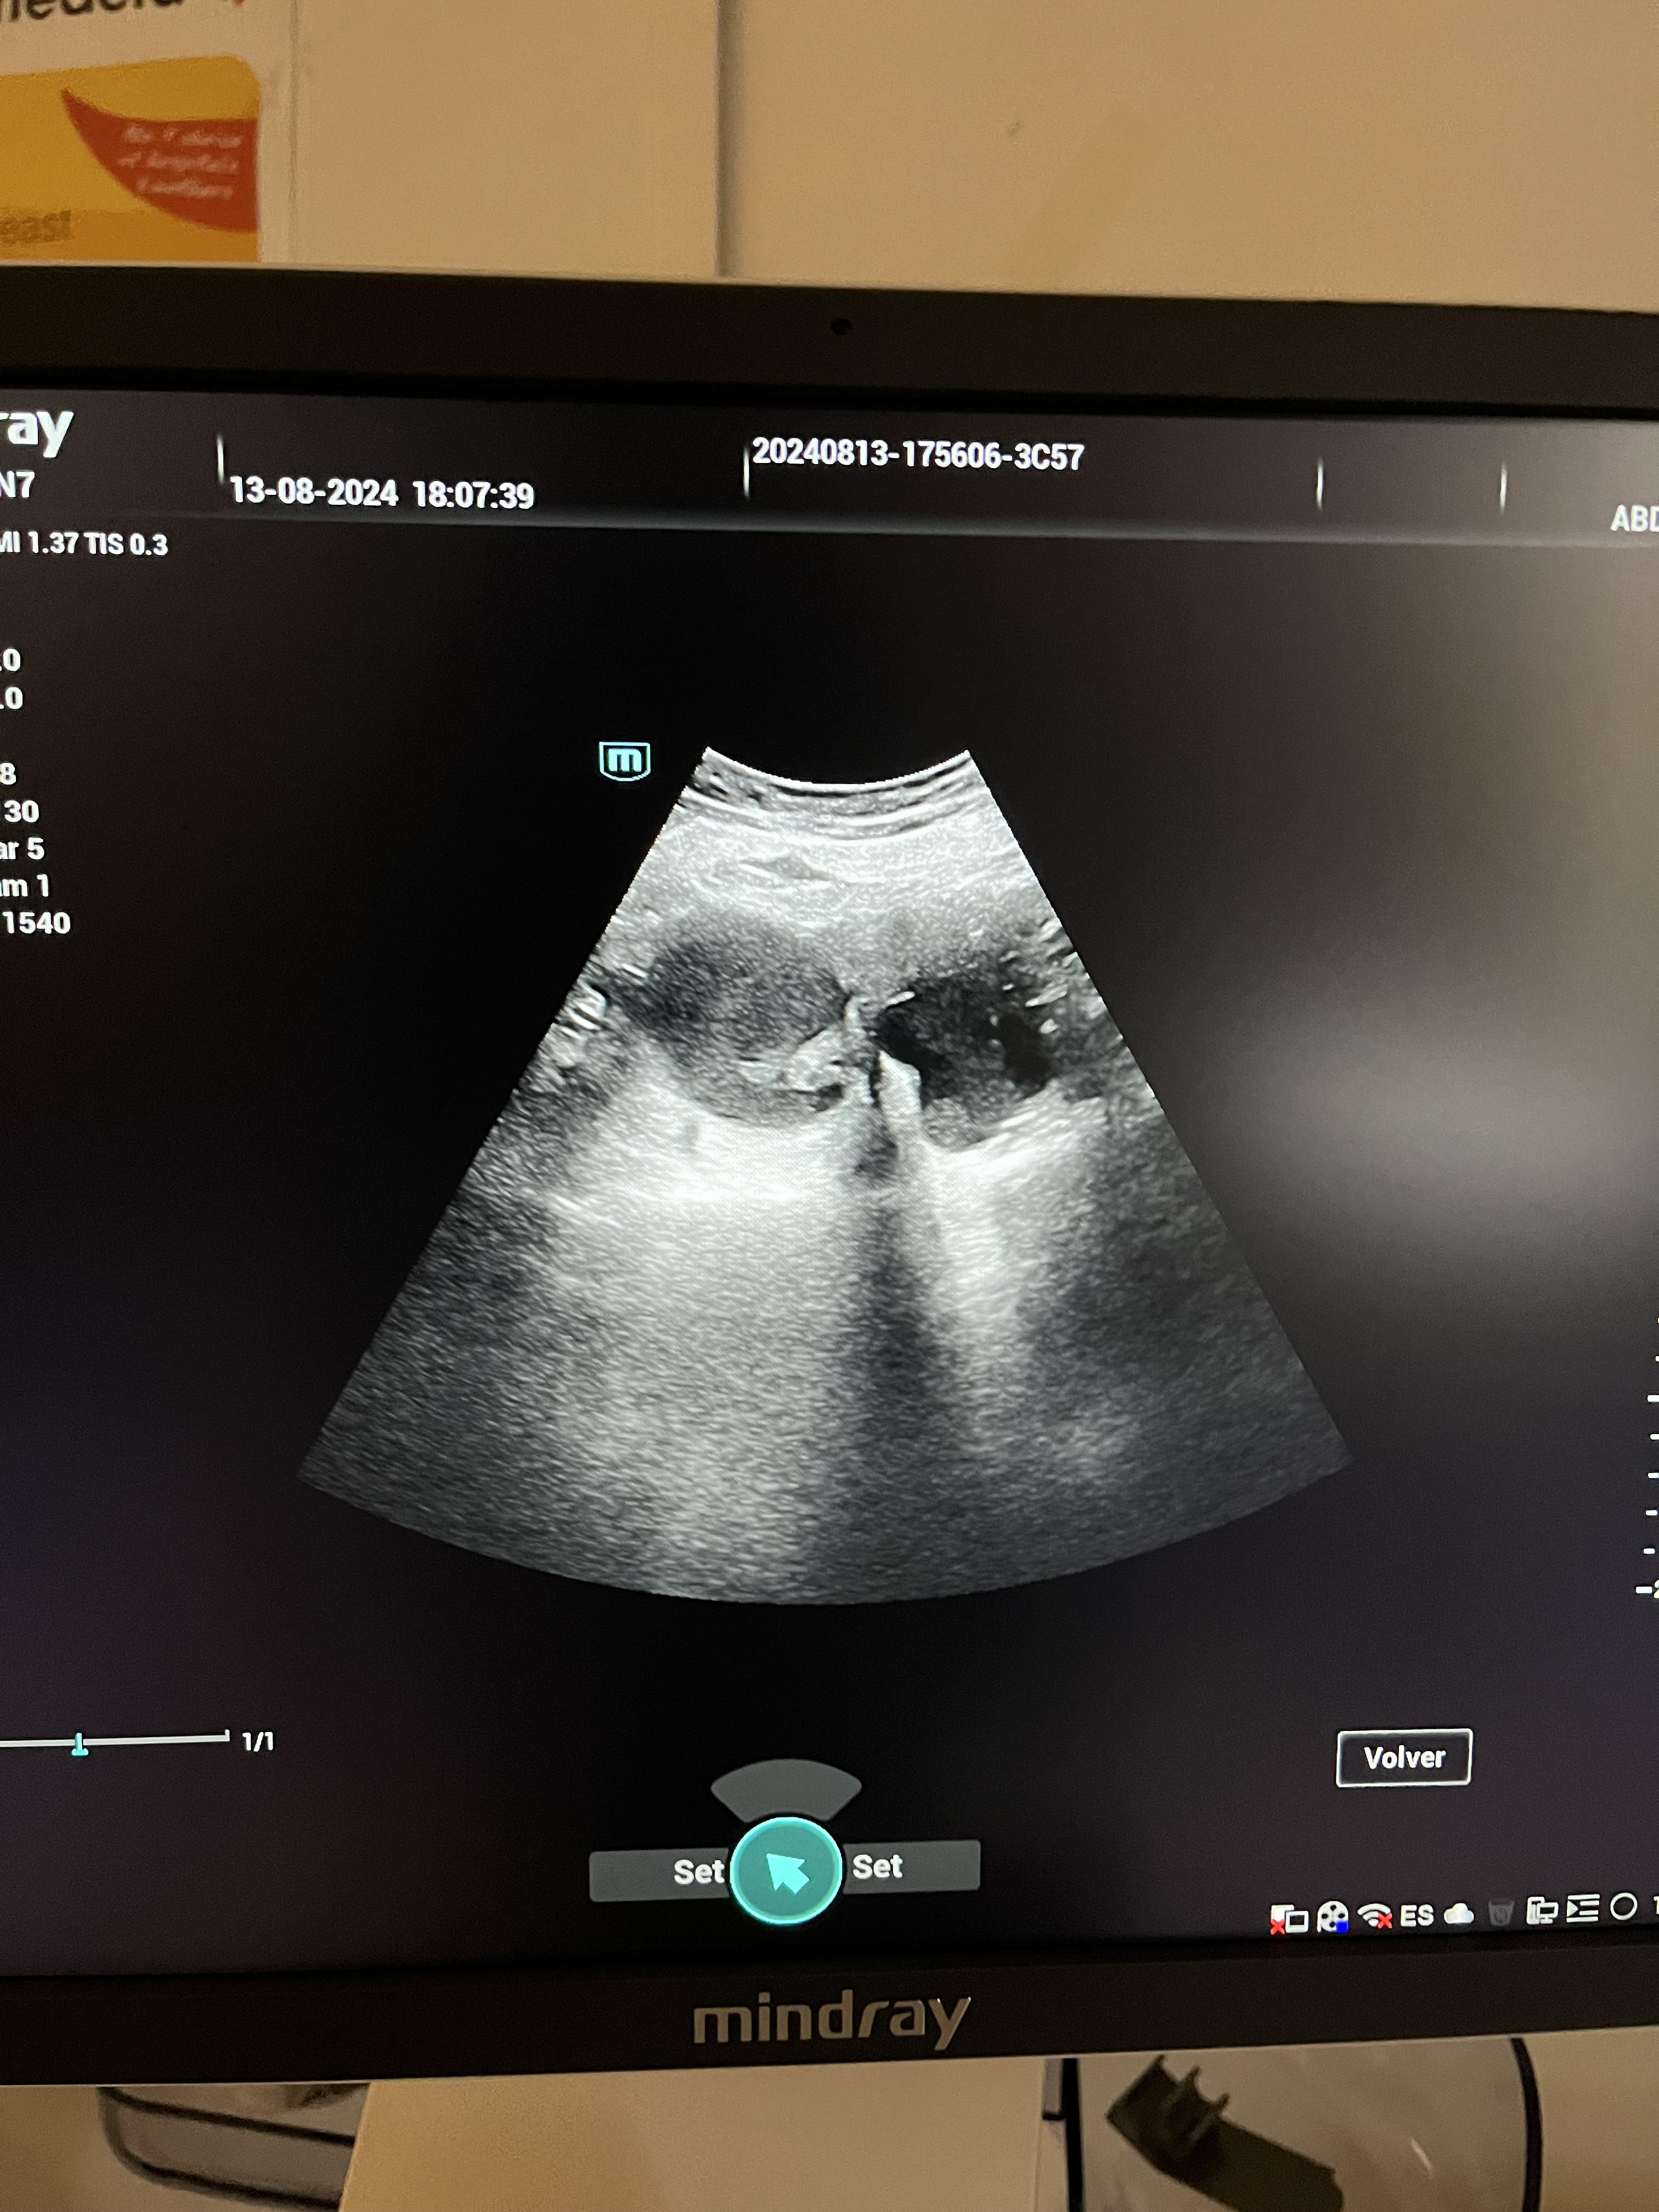

La ecografía revela un útero desplazado por una tumoración quística de contenido hipoecoico de 77 x 63 mm en el lado derecho, sin captación de señal Doppler. La anatomía uterina no se visualiza claramente, y se observa una línea endometrial irregular.

La sospecha principal fue de endometrioma, considerándose el diagnóstico diferencial con mioma uterino. En la valoración hospitalaria, se confirma el hallazgo de endometriosis.

En la valoración hospitalaria mediante ecografía ginecológica reglada, se describe un útero de 90 x 55 x 58 mm con signos de adenomiosis: asimetría miometrial (miometrio anterior de 16 mm y posterior de 33 mm), quistes de la unión miometrial y miometrio dishomogéneo. Cavidad en signo de interrogación (question mark sign), junto con quistes endometriósicos de gran tamaño a nivel axial bilateral, lo que sugiere endometriosis profunda. Se pauta tratamiento con progestágeno, a la espera de evaluar la evolución y considerar la posibilidad de una histerectomía radical con salpingooforectomía bilateral.